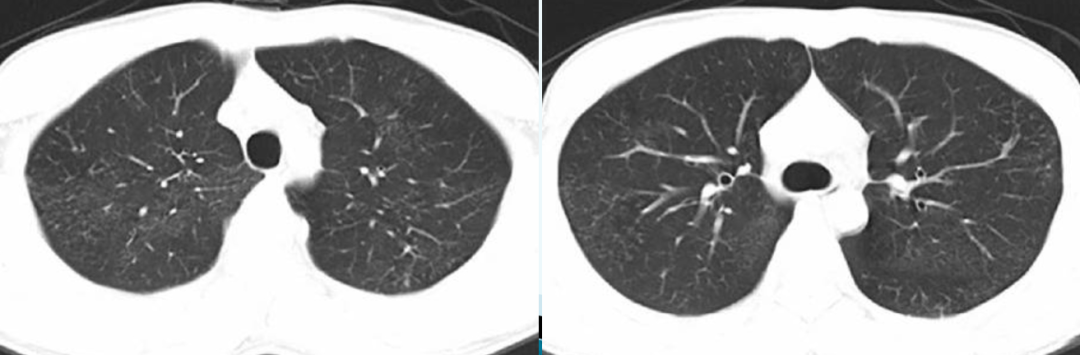

这张CT显示的是经支气管播散的肺结核的典型表现:簇状分布的小叶中心性微结节、新旧不均:

在肺结核的胸部CT上我们经常见到许多微结节形成树芽症。除此之外,在实变比较明显的部位,仔细看它的边缘部分,往往也能找到一些微结节和树芽(箭头),有些还可以形成空洞。

簇状分布的小叶中心性微结节、新旧不均,可伴树芽征或空洞。